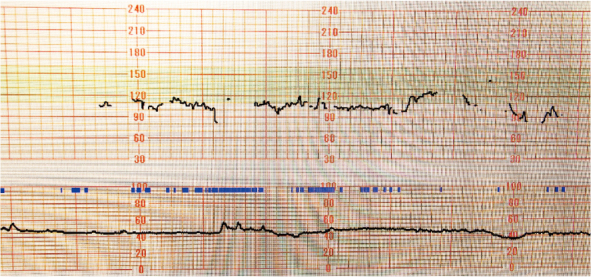

The incidence of Acinetobacter infections has increased in recent years. Acinetobacter infections are resistant to most antibiotics and can be found in hospitalized patients. Pregnancies complicated by severe sepsis or septic shock are associated with a higher rate of preterm labor and delivery, fetal infection, and operative delivery. This case report describes septic shock due to Acinetobacter lwoffii infection in the 31st week of gestation. A 47-year-old woman, with a gestation of 31 weeks and one day, presented with a fever, and signs of bacterial infection on laboratory tests. Although the patient was started on tazobactam/piperacillin, she went into septic shock, and was transferred to our hospital. Cesarean section was performed at a gestation of 31 weeks and 4 days because of severe maternal pneumonia and non-reassuring fetal status. A. lwoffii was detected in blood cultures collected at the previous hospital, and susceptibility to piperacillin and meropenem to A. lwoffii was confirmed. The pneumonia responded to antibiotic treatment and there were no findings of infection in the neonate. Maternal sepsis is an infrequent but important complication, causing significant maternal and fetal morbidity and fetal and neonatal mortality; therefore, early antibiotic therapy is required to improve the clinical outcome.

Abstract Image